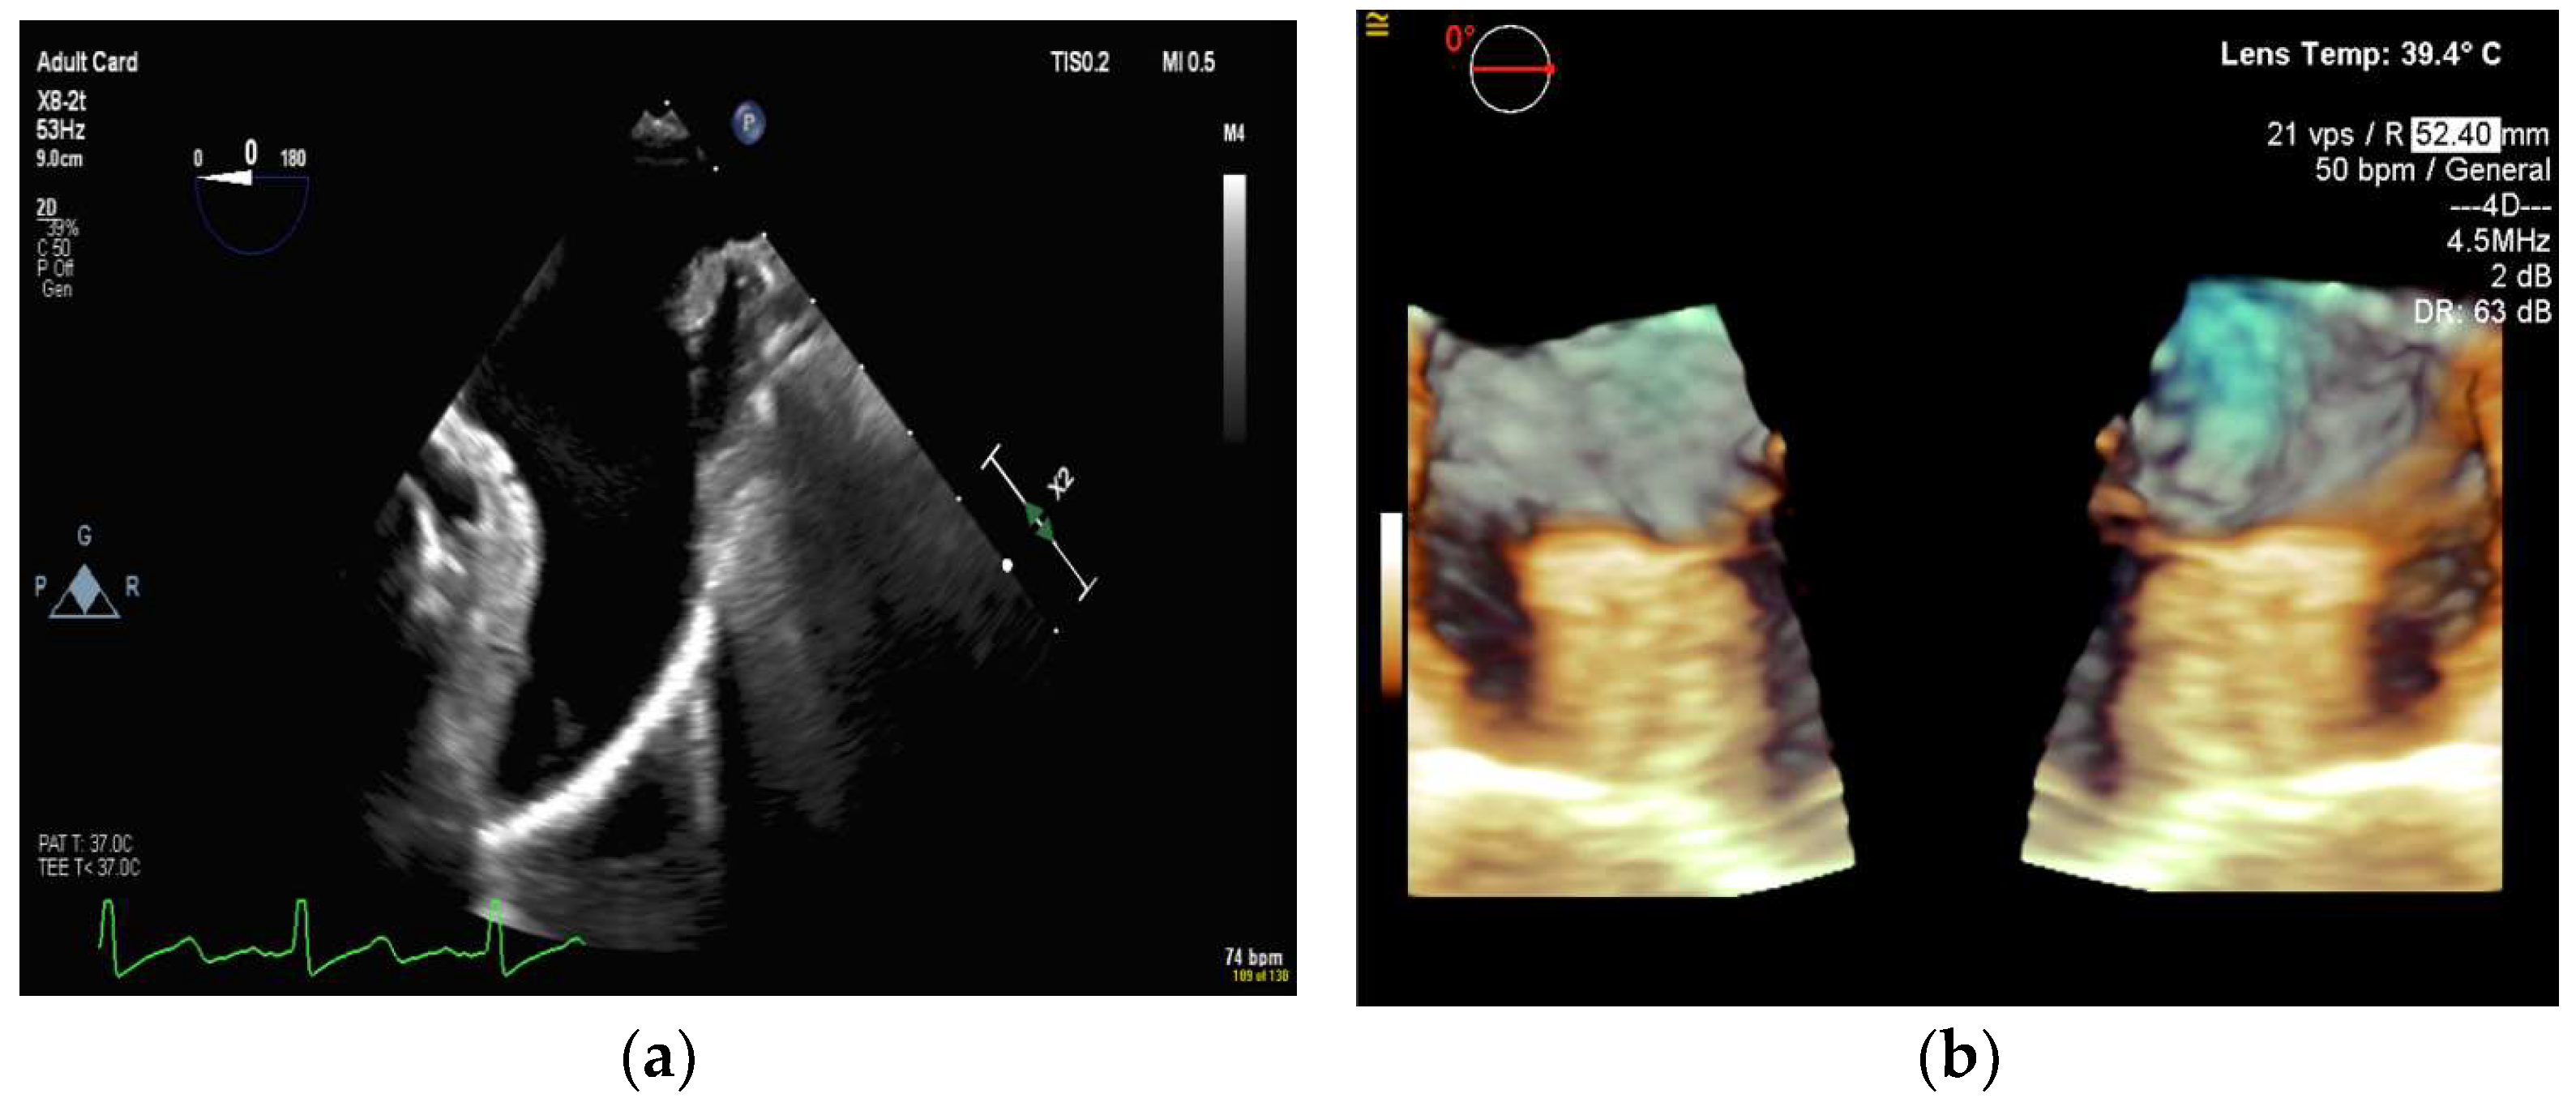

4.2.3. Mitral Valve Repair

4.2.4. Atrial Septal Defect Occlusion